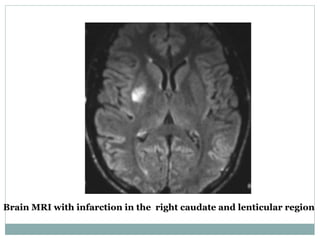

Brain MRI with infarction in the right caudate and lenticular region

Brain MRI withinfarction in the right caudate and lenticular region